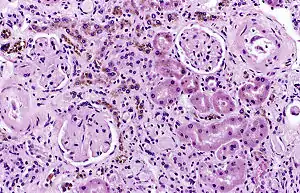

It is only found within cells (as opposed to circulating in blood) and appears to be a complex of ferritin, denatured ferritin and other material.[4][5] The iron within deposits of hemosiderin is very poorly available to supply iron when needed. Hemosiderin can be identified histologically with Perls' Prussian blue stain; iron in hemosiderin turns blue to black when exposed to potassium ferrocyanide.[6] In normal animals, hemosiderin deposits are small and commonly inapparent without special stains. Excessive accumulation of hemosiderin is usually detected within cells of the mononuclear phagocyte system (MPS) or occasionally within epithelial cells of the liver and kidney.

Hemosiderin is most commonly found in macrophages and is especially abundant in situations following hemorrhage, suggesting that its formation may be related to phagocytosis of red blood cells and hemoglobin. Hemosiderin can accumulate in different organs in various diseases.

Hemosiderin often forms after bleeding (haemorrhage).[7] When blood leaves a ruptured blood vessel, the red blood cell dies, and the hemoglobin of the cell is released into the extracellular space. Phagocytic cells (of the mononuclear phagocyte system) called macrophages engulf (phagocytose) the hemoglobin to degrade it, producing hemosiderin and biliverdin. Excessive systemic accumulations of hemosiderin may occur in macrophages in the liver, lungs, spleen, kidneys, lymph nodes, and bone marrow. These accumulations may be caused by excessive red blood cell destruction (haemolysis), excessive iron uptake/hyperferraemia, or decreased iron utilization (e.g., anaemia of copper toxicity) uptake hypoferraemia (which often leads to iron deficiency anemia).

Cellular iron is found as either ferritin or hemosiderin. It is identified in cells by the Perls or Prussian blue reaction, in which ionic iron reacts with acid ferrocyanide to impart a blue color.<Wintrobe's Clinical Hematology>